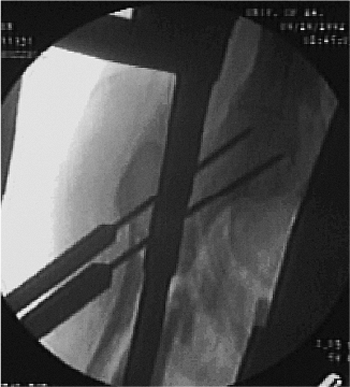

Figure 20.16. A,B.

Rotation of proximal drill guide to center guide for correct anteversion of screws into femoral head; drill guide should bisect the femoral head on the true lateral radiographic view. |

Figure 20.17. Lateral fluoroscopic view with bisection of femoral head through use of drill guide for correct screw position.